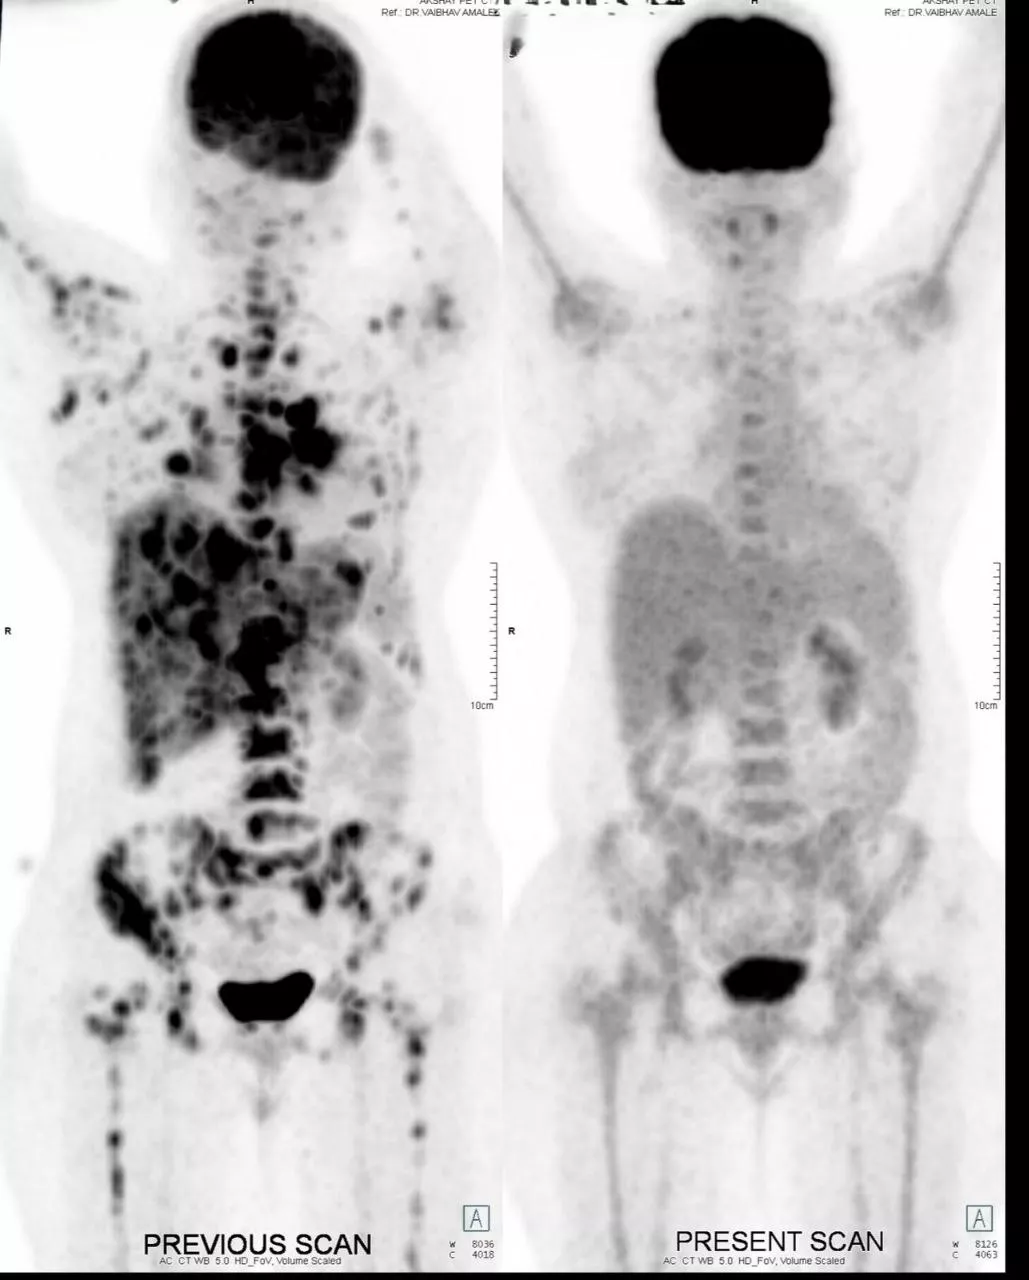

Patient is a 50 year female, Her2 positive metastatic breast cancer. She was diagnosed 2 years back with breast cancer. On diagnosis she was having lung metastatis. She received first line therapy with Paclitaxel and Trastuzumab. After one and half years, she had progression. She received second line treatment with Cap. Lapatinib and Tab. Capecitabine. She responded for 6 months. After 6 months she again progressed with new liver lesions, chest wall lesions and brain lesions. She was symptomatic for brain metastasis- headache, fatigue. She had mild derangement of liver function with elevated SGPT and SGOT, tender hepatomegaly. At this time we treated her with Inj. Trastuzumab Deruxtecan every 21 days. After 1 cycle she showed clinical improvement with reduced headaches and abdominal pain. After 2nd cycle she was almost asymptomatic, LFTs normalised. After 6 cycles, PET scan is showing Complete metabolic response. Brain lesions are metabolically inactive - resolved. She is currently asymptomatic and continuing same treatment.